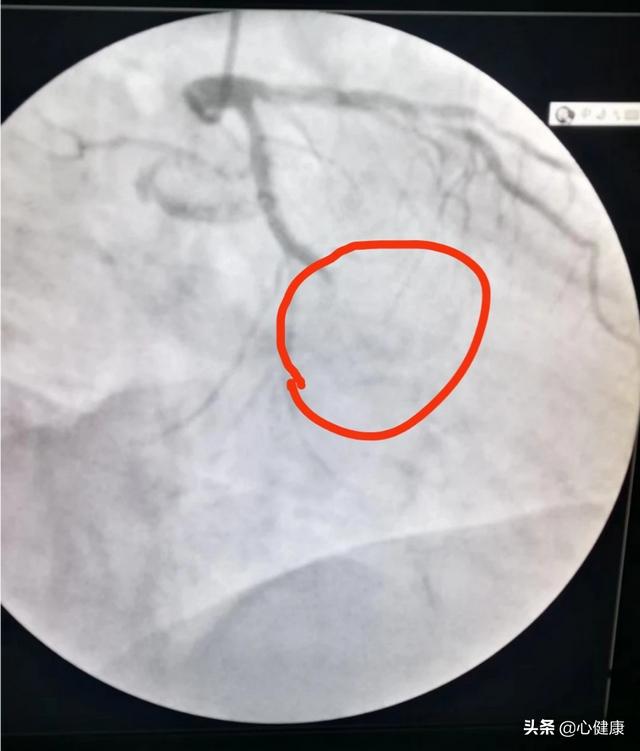

2, l'existence de lésions critiques, telles que l'imagerie d'origine, qui révèle une sténose de 70 à 80 % environ, qui peut être stentée ou non, et qui décide finalement de ne pas poser de stent, puis, après un an, en fonction de la situation, de revérifier l'imagerie, pour voir s'il y a des progrès.

2. 70% de sténose des lésions critiques résiduelles dans les vaisseaux non endigués (avec ou sans endoprothèse) ;

Malgré les progrès de l'industrie du stent et des techniques chirurgicales, le taux de resténose du stent est encore de l'ordre de 5 % (contre environ 20 % les années précédentes). Ces patients présentent un risque élevé de resténose et le chirurgien leur demande souvent de passer une imagerie de contrôle 6 à 9 mois ou 1 an après l'intervention.L'objectif est principalement : 1. de clarifier la situation de l'endoprothèse, de déterminer s'il y a prolifération et resténose à l'intérieur de l'endoprothèse ? 2. de déterminer si les lésions critiques restantes non traitées s'aggravent encore, et s'il y a aggravation, de la traiter à temps, afin d'éviter l'infarctus du myocarde, qui n'est pas encore une menace vitale !